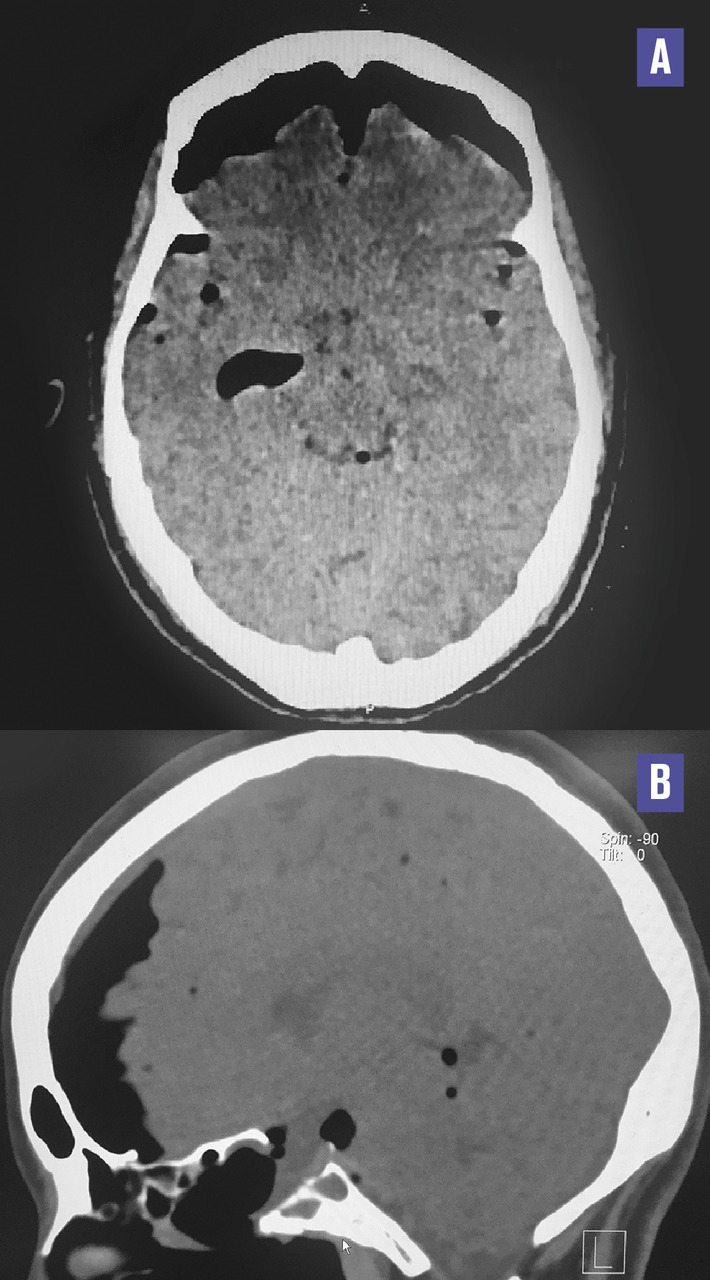

Cette femme de 38 ans consultait pour des céphalées en casque évoluant depuis une semaine. La patiente précisait avoir une rhinorrhée antérieure depuis une intervention neurochirurgicale sur adénome hypophysaire réalisée un mois auparavant. L’examen ne notait ni atteinte des paires crâniennes ni céphalée orthostatique. La patiente était apyrétique et son bilan biologique ne montrait pas de syndrome inflammatoire ou infectieux. Une liquorrhée cérébrospinale était visualisée au contact du sphénoïde à la rhinoscopie. La tomodensitométrie cérébrale était normale (fig. 1 ). La patiente était hospitalisée et, le soir même, chutait dans la salle de bains. Une nouvelle tomodensitométrie (48 h après la première) montrait une pneumencéphalie diffuse témoignant d’une brèche méningée (fig. 2 ). La chute a probablement accentué la brèche, occasionnant la pneumencéphalie secondaire.